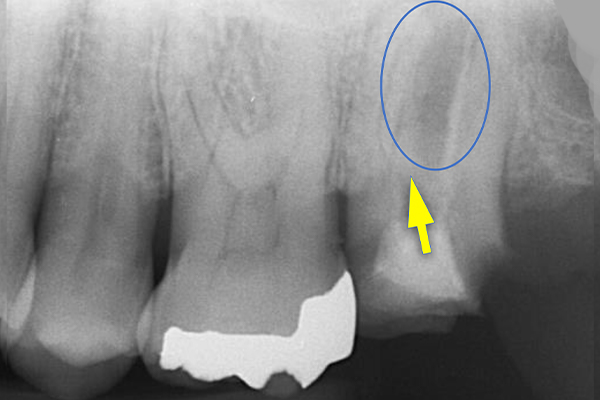

2.初診時エックス線写真

左上の1番奥の歯はすでに神経がとってあり、

大きなむし歯を認め根分岐部の歯周ポケットは8mmでした。

今回の症例では、歯根の途中にパーフォレーション(穴があいている)が認められ(黄矢印)、根の間の骨(青丸)が溶けていました(根分岐部病変)。

パーフォレーションは抜歯となってもおかしくないですが、患者さんは歯の保存を強く希望されました。